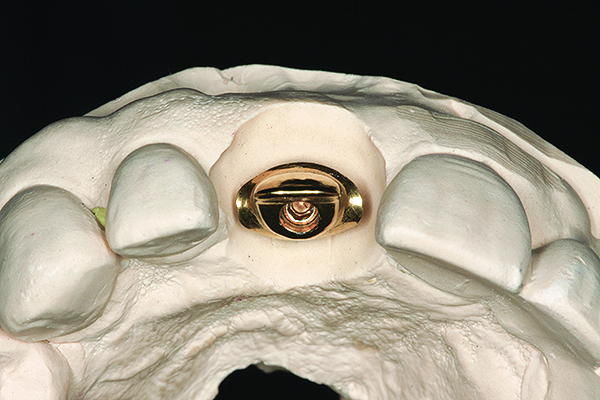

The implant impression, along with a cast of the opposing arch and shade, were sent to a commercial dental laboratory for fabrication of a master cast. A signed work order and the master cast were then sent to the BellaTek® Production Center (BIOMET 3i) for a lab-designed abutment (LDA) (Figure 14). A BellaTek® abutment was milled from a solid blank of titanium, and a gold-colored titanium-nitride coating was applied to impart a warm color through the thin marginal peri-implant tissues.

Fig 14. The virtually designed abutment.

Figure 14

Fig 15. The master cast and definitive titanium-nitride–coated abutment.

Figure 15